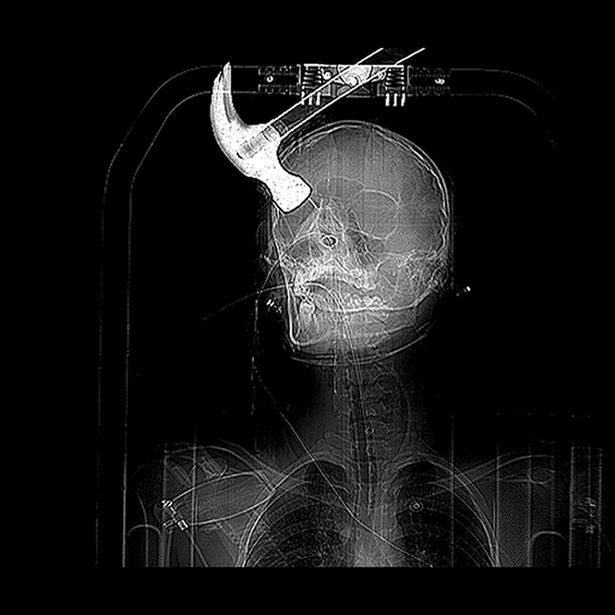

Рентгеновский снимок: